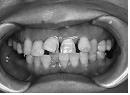

このようにだんだん崩れていきます。

歯茎が下がって歯が伸びたように見えます。

右上の歯が下の歯に突き上げられて飛び出てきています。

本来の位置から列を乱して飛び出したので、隣あう歯との間に隙間が出来てきています。

いきなり揺れだして抜け落ちてしまう場合もあります。

同じ運命を辿る事となります。